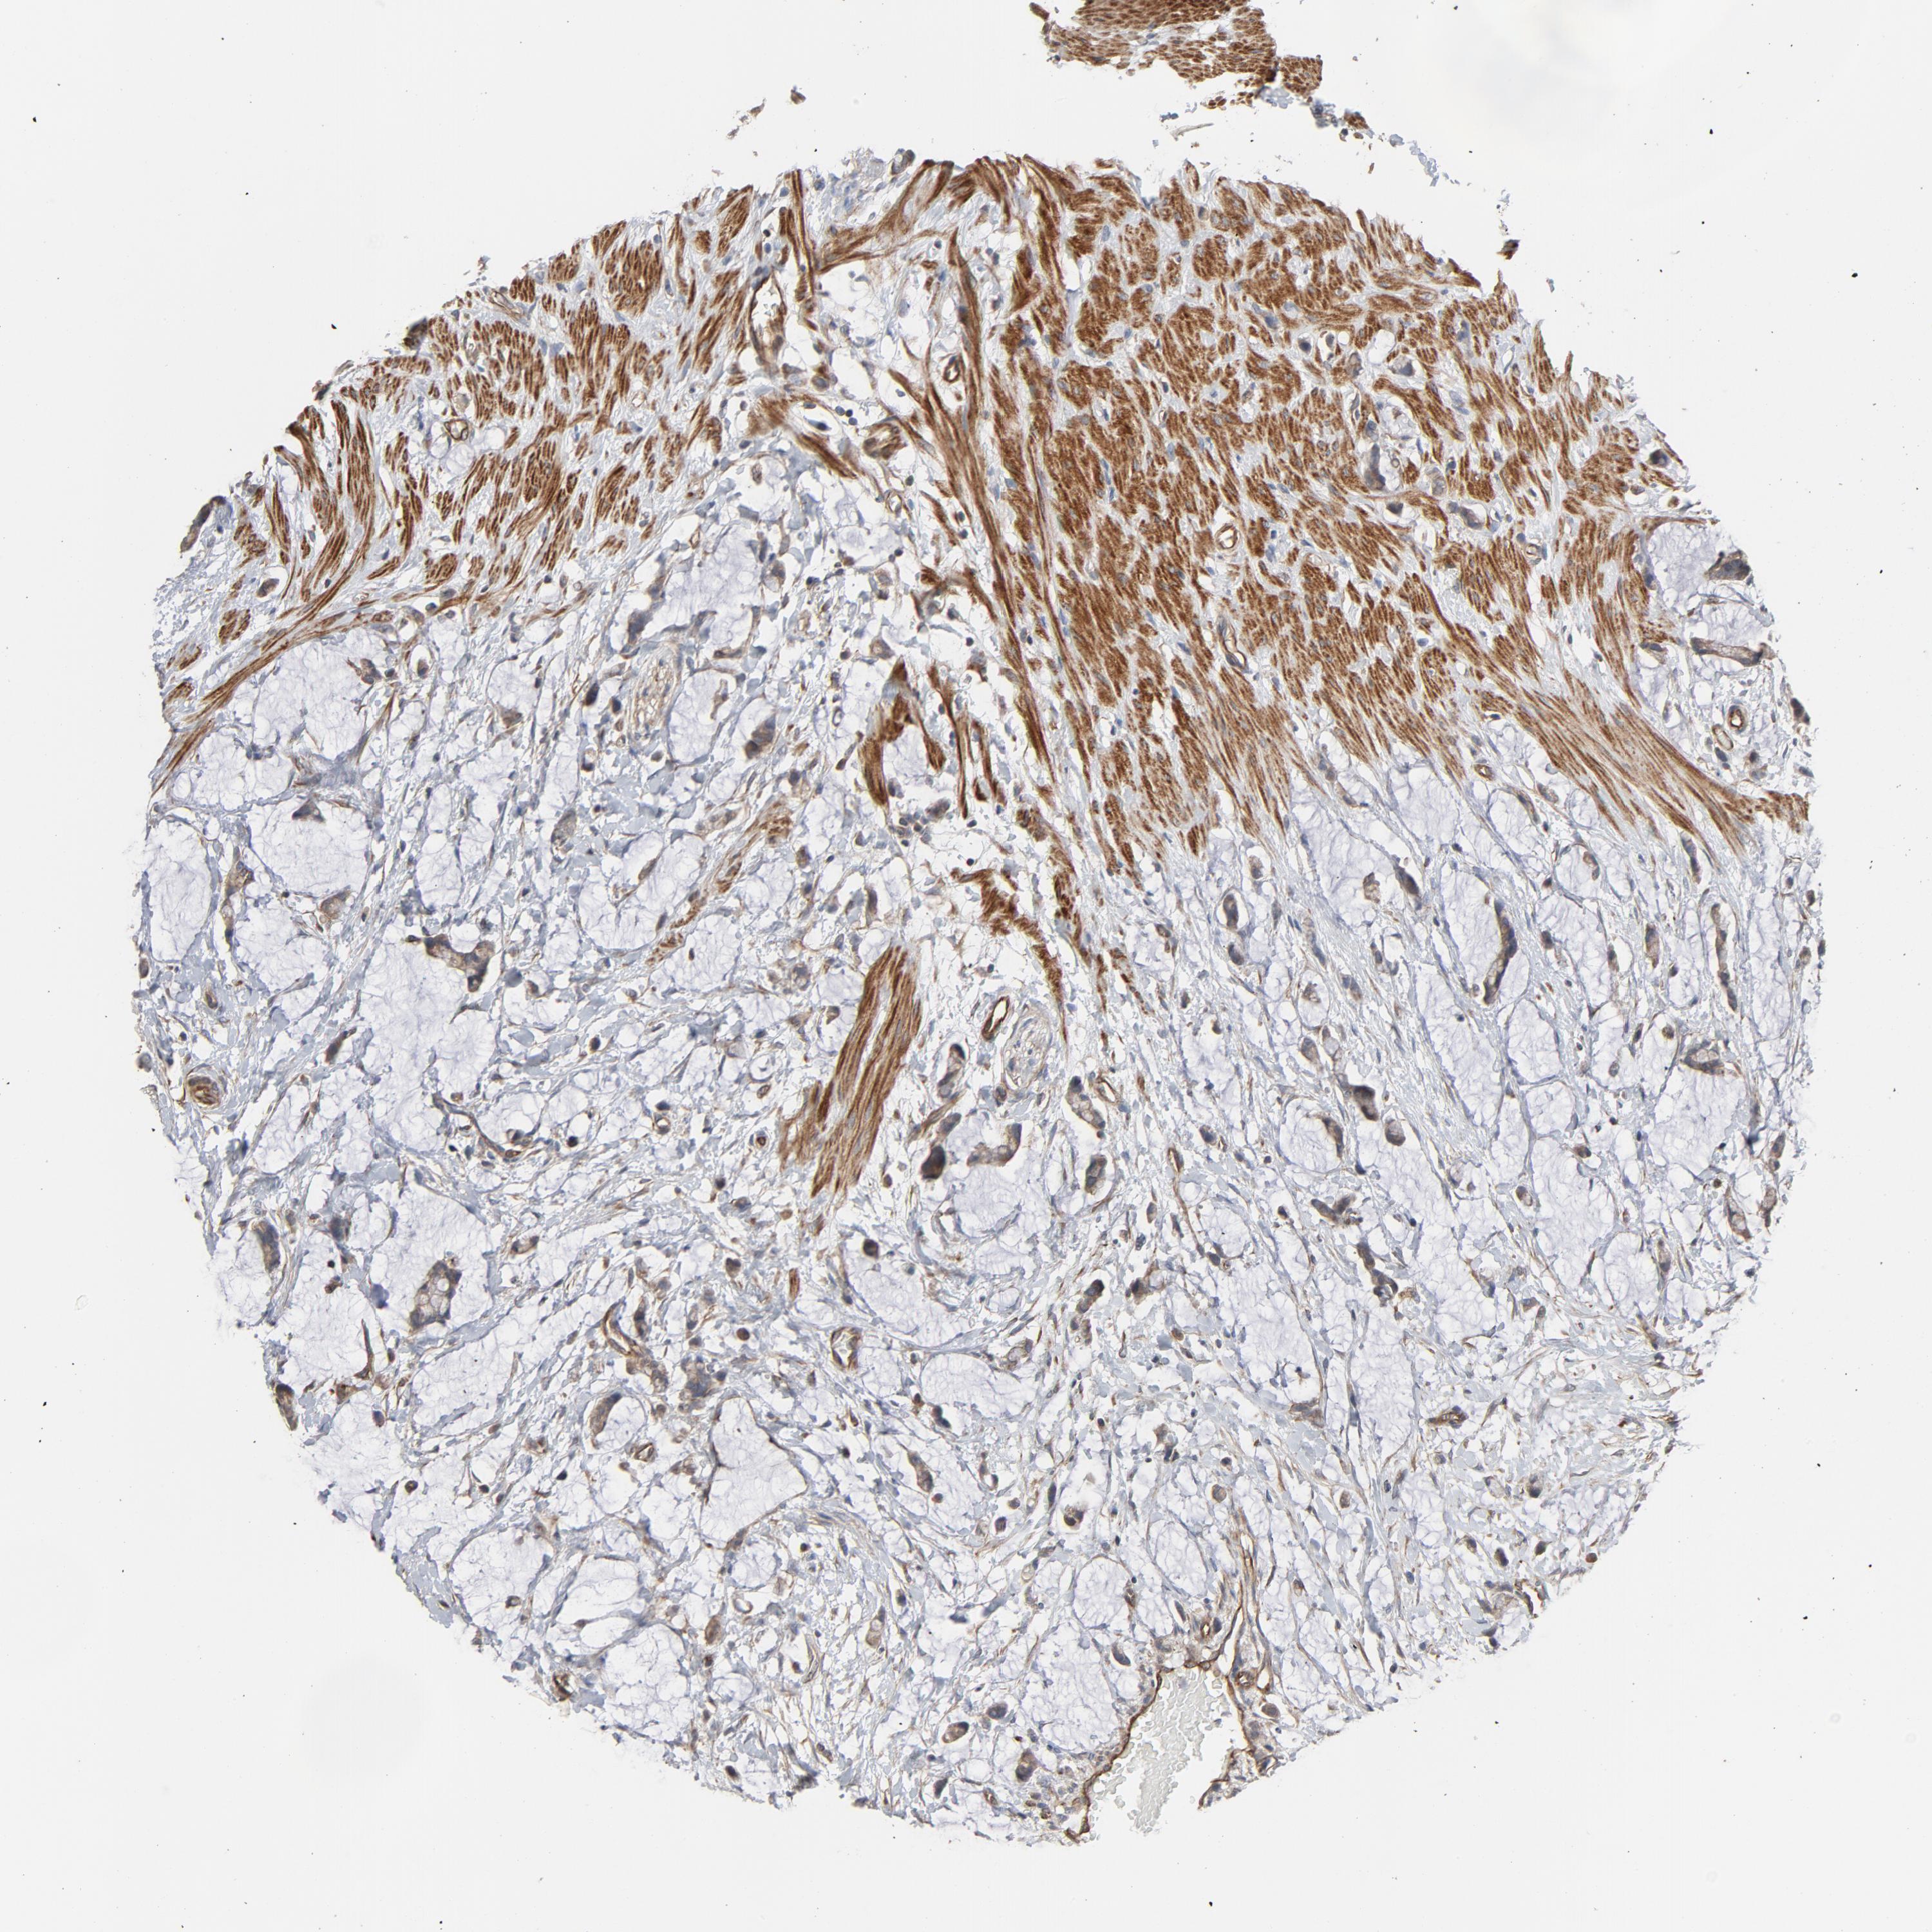

CANCER COLORECTAL CANCER Show tissue menu

Colorectal cancer

Rectum adenocarcinoma